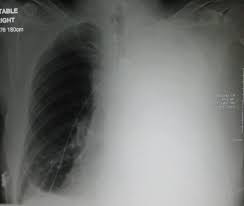

انصباب جنبي ويكيبيديا